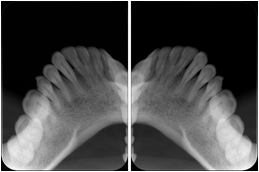

2. A patient requests cosmetic surgery to enhance their facial appearance. The case requires consultation between an orthodontist in New York and an oral surgeon in California. The cephalometric series of 2D projections constructed from the volumetric CT data that is used for the discussion is arranged by a Structured Display for transfer between the two practitioners.

Cephalometric Series Structured Display

Figure OO-2. Cephalometric Series Structured Display